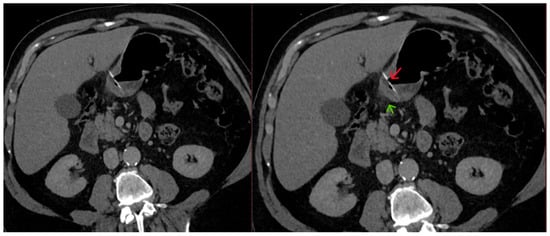

2. Case Report